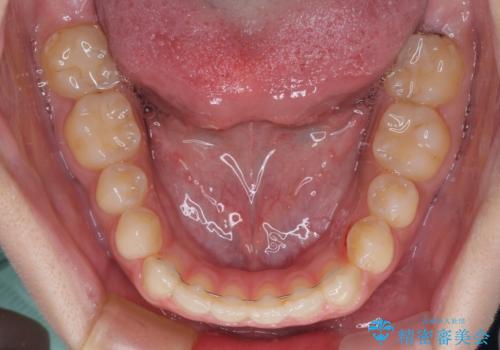

- インビザライン

- 1年10ヶ月

- 10-30回

仕上がりとしては、もう少し上下前歯を接触させたかったのですが、ここまで改善されたことで患者様は大変満足され、治療を終えることとなりました。